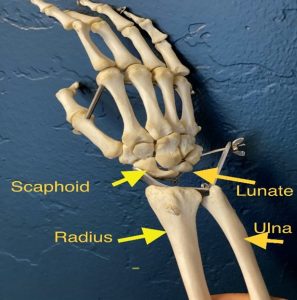

آناتومی استخوان اسکافوئید :

استخوان اسکافوئید( Scaphoid ) بزرگترین استخوان ردیف پروکسیمال استخوان های مچ است و نام آن از واژه یونانی اسکافوس به معنی قایق گرفته شده است که این نام گذاری بدلیل ظاهر قایقی شکل آن است. در سمت خارجی مچ قرار دارد و سطوح مفصلی زیادی دارد و بیشتر از ۸۰ درصد آن با غضروف پوشیده شده است .

در سطح کف دستی آن یک تکمه قرار دارد که میتواند در قاعده انفیه دان تشریحی لمس شود.

اسکافوئید( Scaphoid ) همراه با بقیه استخوانهای مچ دست یک ساختار استخوانی برای مچ و دست فراهم کنند. این استخوان همراه با استخوانهای لونیت و سطح دیستال رادیوس و اولنا در حرکات مچ اثر میگذارند ( شکل ۳ ) . این استخوان لبه خارجی تونل کارپال را تشکیل داده و با پنج استخوان رادیوس، تراپیزوئید ، تراپیزیوم ، کپتیت و لونیت مفصل میشود . همچنین تکمه آن محلی برای اتصال لیگامان عرضی مچ دست و در مواردی فیبرهایی از عضله ابداکتور پولیسیس برویس است. لیگامان رادیال کلترال به سطح خارجی ان متصل میشود.

( شکل ۳ ) استخوان های مچ دست .